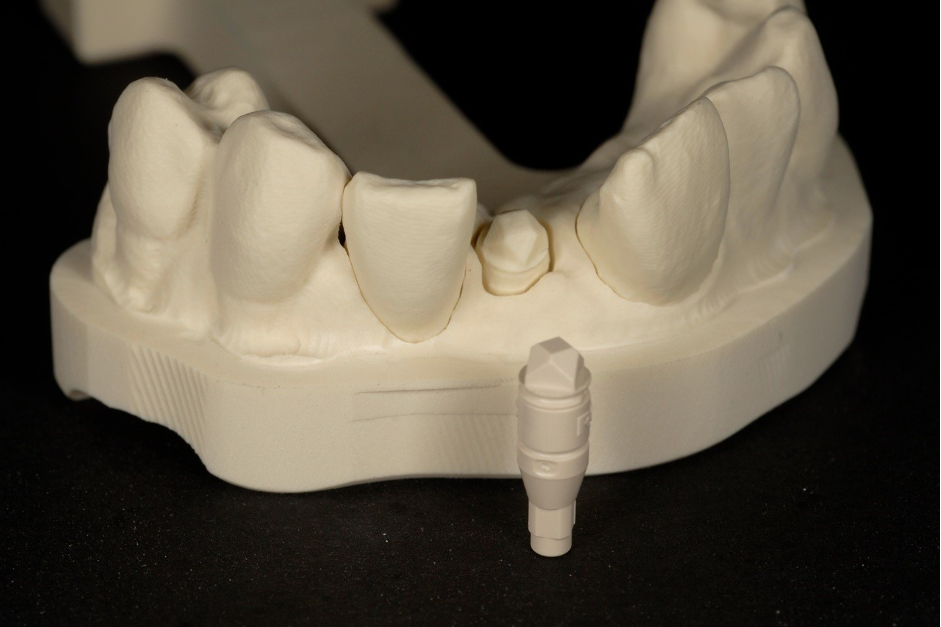

What happens if you have a case like the one below where you have preps and implants?

This is an example of a bigger case – one where we wanted to be able to incorporate the fixture position of the implants into the model.

To solve this puzzle, we had to use Kiwi ingenuity.

The closest translation of this New Zealand saying would be ‘thinking outside the box’.

As a result, the benefits we were seeing in our conventional workflows could also be applied to our implant cases.

You can see in the series of images below, courtesy of Ashley Bryne, how we did this.

So now we had the benefits we were seeing with routine work and in our implant cases/combined cases.